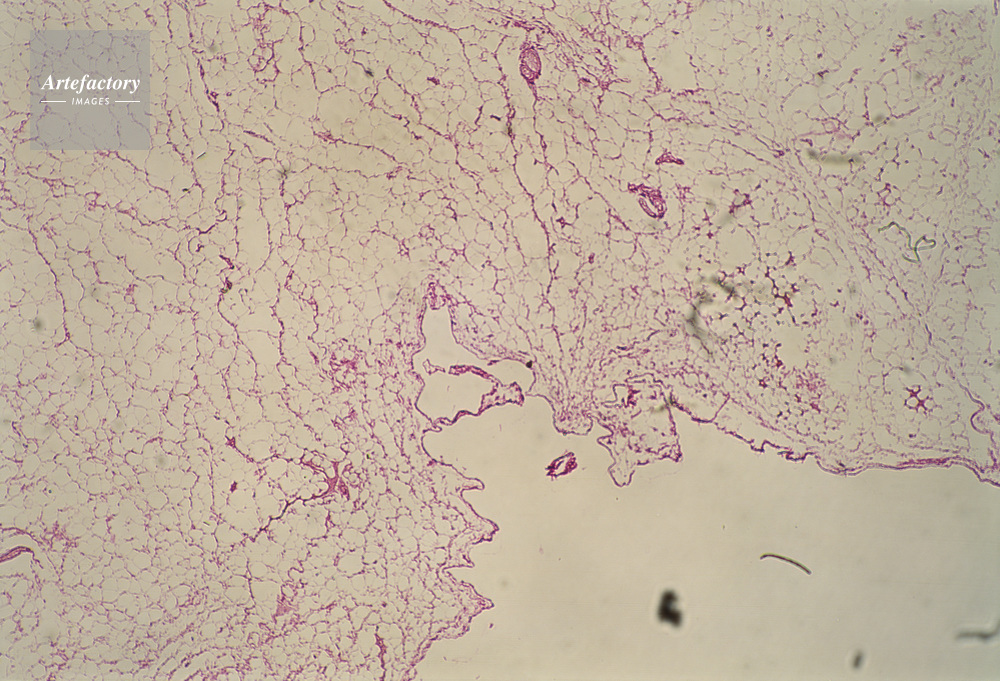

| 作品タイトル | 顕微鏡写真 | モデルリリース | なし | |

| キャプション | 脂肪組,人間,10倍 | 制限事項 | ||